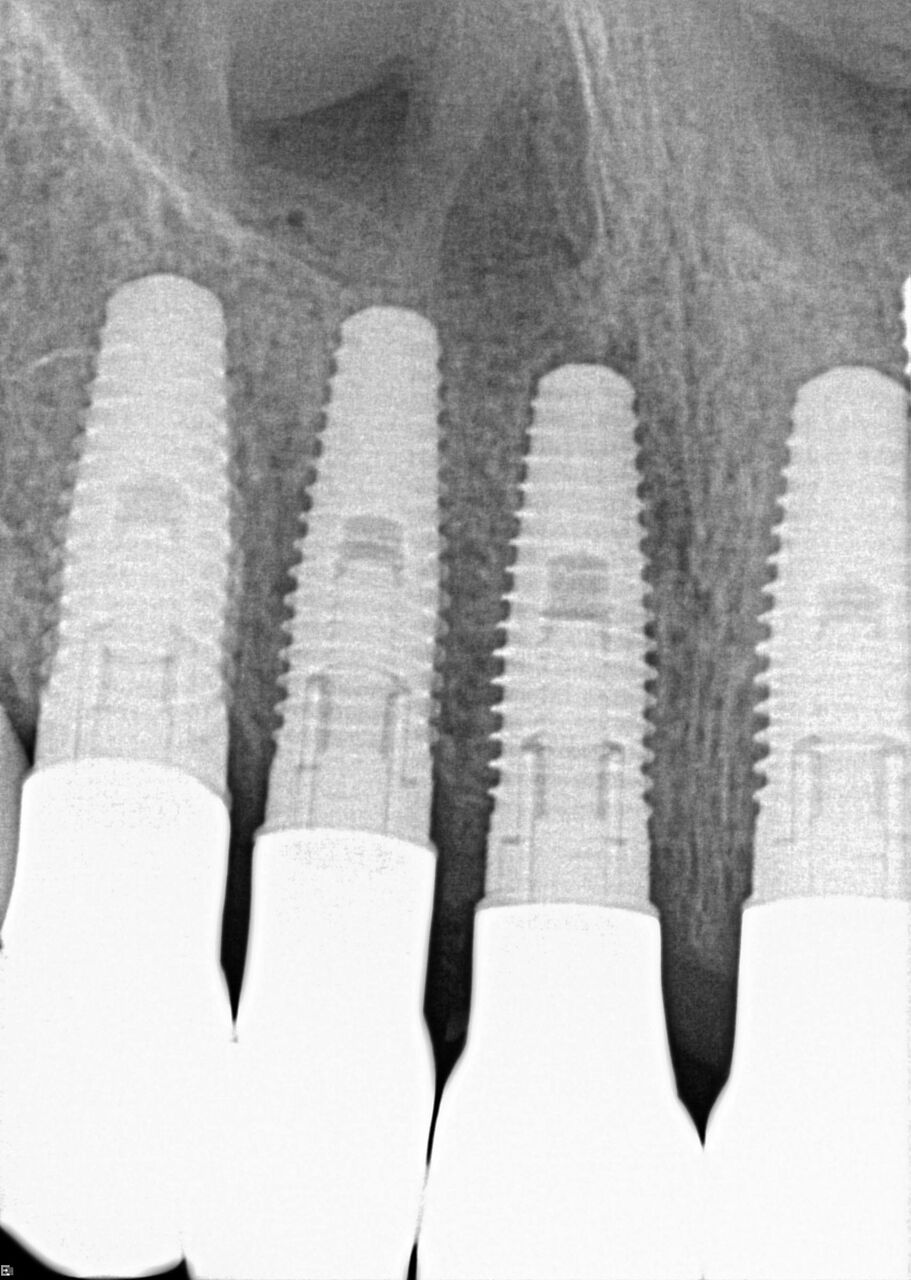

(24.) Radiograph of postoperative individual crowns on Nos. 6 through 10.

Figure 24

(25.) Radiograph of postoperative individual crowns on Nos. 6 through 10.

Figure 25

(26.) Postoperative individual implant restorations on Nos. 6 through 10.

Figure 26

A 42-year-old man presented with a very loose bridge on Nos. 6 through 9 with periodontally compromised retainers on Nos. 6 and 9 (Figure 17 through Figure 19), and endodontically involved No. 10 with a calcified canal. Teeth Nos. 6, 9, and 10 were extracted, the sockets fully debrided, and pontic soft tissue on Nos. 7 and 8 sculpted to be symmetrical in soft tissue contour with the contralateral lateral incisor and central incisor locations. Implants were secured in position Nos. 6 through 10 (Figure 20) in excess of 45 Ncm, the bone was milled to provide unimpeded seating of temporary abutments, and temporary crowns were fabricated chairside and adjusted to be out of occlusion in centric relation and all excursions. The temporary crowns were cemented after extrusion of excess cement extraorally and the patient was prescribed antibiotics, analgesics, and instructed in postoperative care particular to immediately provisionally restored implants. At 6 months, integration was confirmed (Figure 20 through Figure 23) and after placement of scanning abutments, the implants and soft tissues were scanned. Final crowns were fabricated from the scanned images and were cemented after extrusion of excess cement extraorally (Figure 24 through Figure 26), and oral hygiene procedures were reviewed.